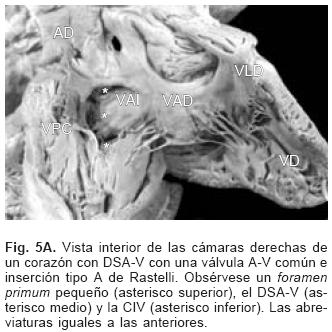

De los sesenta y cinco corazones con válvula común en veinticinco se determinaron los tipos de la clasificación de Rastelli que fueron los siguientes: en once (44%) las valvas anterosuperiores derecha e izquierda se insertaron a través de sus cuerdas tendinosas sobre la cresta del tabique ventricular y la CIV se ubicó en los espacios intercordales (tipo A de Rastelli) (Figs. 1A y 5A). En un espécimen las valvas anterosu–periores izquierda (valva puente) y derecha se insertaron sobre la cara derecha del tabique ventricular por debajo de su cresta (Fig. 5B) y en otro dicha inserción se hizo en la parte superior del cuerpo de la trabécula septomarginal (Fig. 5C). En ocho corazones (32%) la inserción de esas valvas se estableció en un músculo papilar situado en la unión del tabique ventricular con la pared libre del ventrículo derecho y la valva anterosuperior izquierda pasó como puente por encima de la CIV (tipo B de Rastelli) (Figs. 1B y 5D) y en seis corazones (24%) la inserción de las valvas anterosuperior izquierda (valva puente) y derecha se insertaron en un músculo papilar de la pared libre del ventrículo derecho y esta valva se ubicó por encima de la CIV (tipo C de Rastelli) (Figs. 1C y 5E). En los cuarenta corazones restantes no fue posible determinar los tipos de Rastelli debido a que treinta y tres de ellos presentaron doble entrada ventricular (Fig. 6A) dos tuvieron modificaciones anatómicas generadas por la cirugía y cinco por presentar mutilaciones realizadas durante la necropsia. Los cinco especímenes con dos válvulas separadas tuvieron estructura trifoliada dentro de la unión A–V común (Figs. 3B y 6B); la válvula A–V izquierda mostró una valva lateral y dos septales anterior y posterior unidas a la cresta del tabique ventricular, lo que obliteró la CIV (Fig. 6C). La válvula A–V derecha mostró una valva septal displásica, una anterior y una posterior (Figs. 3B y 6B).

En cuanto a la clasificación de Rastelli16 existe en realidad un espectro de grados de inserción de las cuerdas tendinosas de la valva "puente" en la que los tipos A, B y C constituyen los sitios más frecuentes de esa inserción y se debe considerar la existencia de inserciones intermedias entre ellos como se evidencia en el presente trabajo. Los DSA–V presentes en la doble entrada ventricular ya sea izquierda, derecha o a ventrículoúnico,escapan a la clasificacióndeRastelliya que las valvas anterosuperior–izquierda (valva puente) y la anterosuperior derecha están contenidas en una sola cavidad ventricular. En las formas balanceadas de esta cardiopatía la válvula A–V común se conecta a partes iguales con ambos ventrículos. Las formas de dominancia ventricular se expresan cuando la válvula A–V común se conecta preponderantemente con un ventrículo, en la dominancia de tipo derecho el ventrículo izquierdo es pequeño, ya que posee menos superficie valvular, mientras que en la dominancia de tipo izquierdo es el ventrículo derecho el de menor tamaño. En este concepto se consideran las dobles entradas a ventrículo derecho o al izquierdo.30